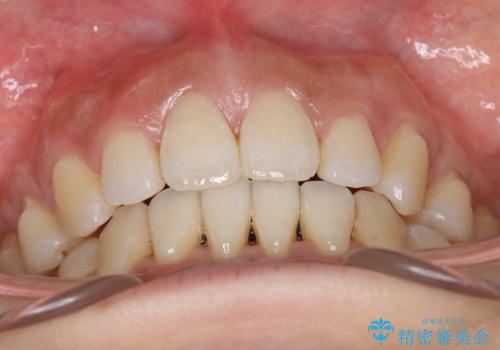

- 出っ歯がきになるとのことで来院されました。

矯正を開始する前から歯肉退縮があり、悪化しないように注意しながら矯正治療を行いました。